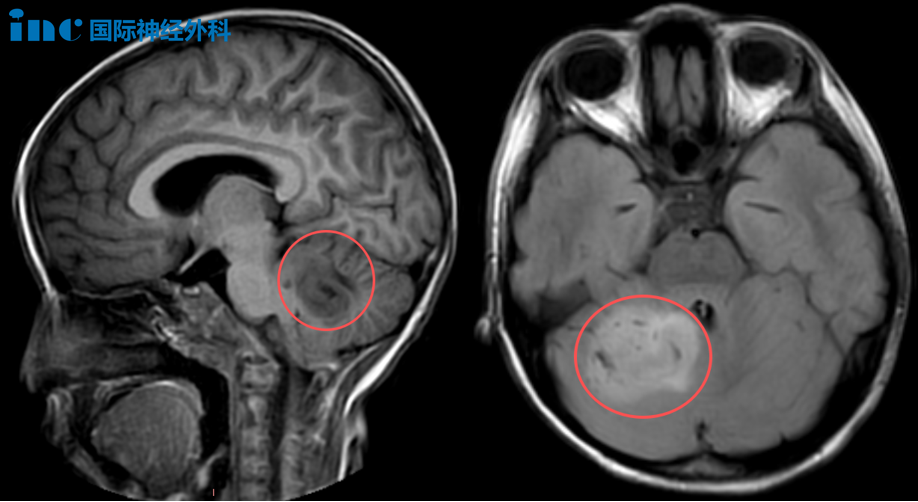

6岁女孩乐乐,在1个多月前被查出小脑占位,一度令乐乐一家陷入前所未有的迷茫和无助中。核磁上巨大的肿瘤,让原本活泼开朗的女儿变得头晕头痛、嗜睡……而导致这一切的罪魁祸首却一直得不到解决,这对乐乐父母来说,每一天都是煎熬。